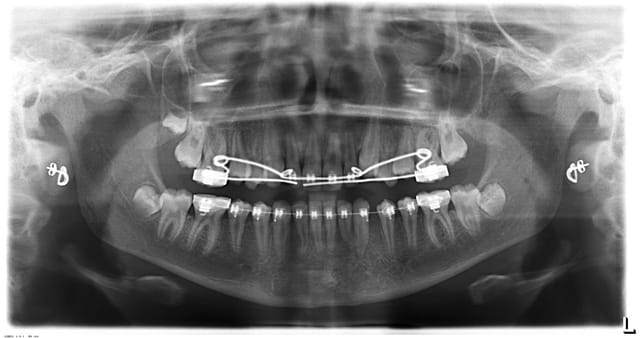

petit cas, commencé il y a quelques années.

C'est de l'ortho mais je suis omnipraticien.

Le cas ou j'ai le plus galéré ( classe 3 et surtout 43 incluse ), mais qui m'apporte beaucoup de satisfaction.

fille d'un ami en plus!